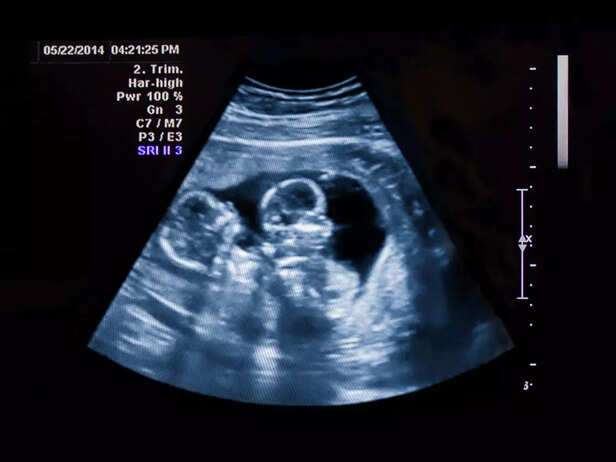

twin ultrasound

There are two primary types of multiple pregnancies: dizygotic (fraternal) and monozygotic (identical). Understanding the differences between these types is essential when discussing potential complications.